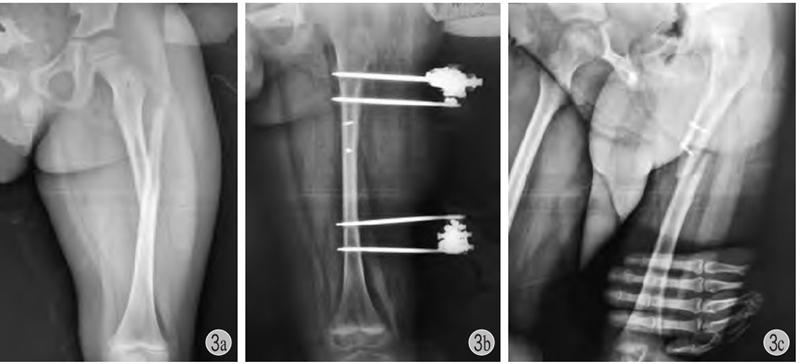

(1) 一般来说小年龄患儿的干部骨折不需要切开复位内固定,以股骨干为例,4 岁之前通常不用内固定治疗,4~10 岁之间通常选用弹性针固定,11 岁以上一般考虑青少年锁定髓内钉 (图3)。(2) 锁骨骨折儿童期通常不需要切开复位内固定 (图4)。在面对家长强烈的手术意愿下,应该与家长沟通选择合适的治疗方式,坚守儿童骨折的治疗原则。倘若因违背手术适应证而造成术后骨不连、骨髓炎等严重并发症,不仅患者的利益受到损害,更可能会引起诉讼纠纷。

图3 患儿 男 7岁

a、b:左股骨干骨折,应尽量闭合复位应用弹性针或肌肉下接骨板固定,该患儿切开复位,局部螺钉+外架固定;c:拆除外架后3个月发生再骨折